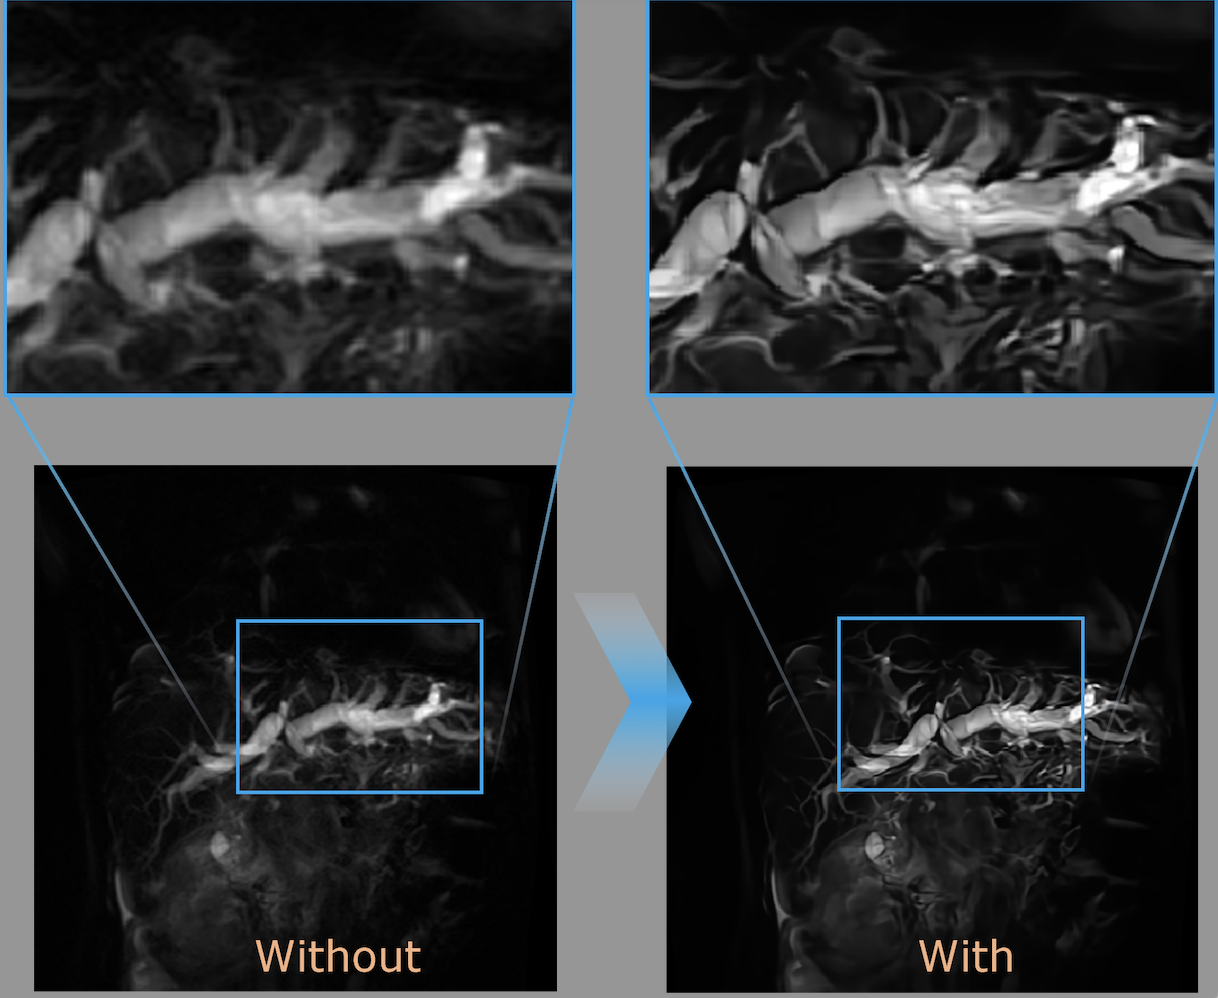

HARP

Được thiết kế chuyên biệt cho bệnh nhân có cấy ghép kim loại, giúp thu được hình ảnh rõ nét hơn